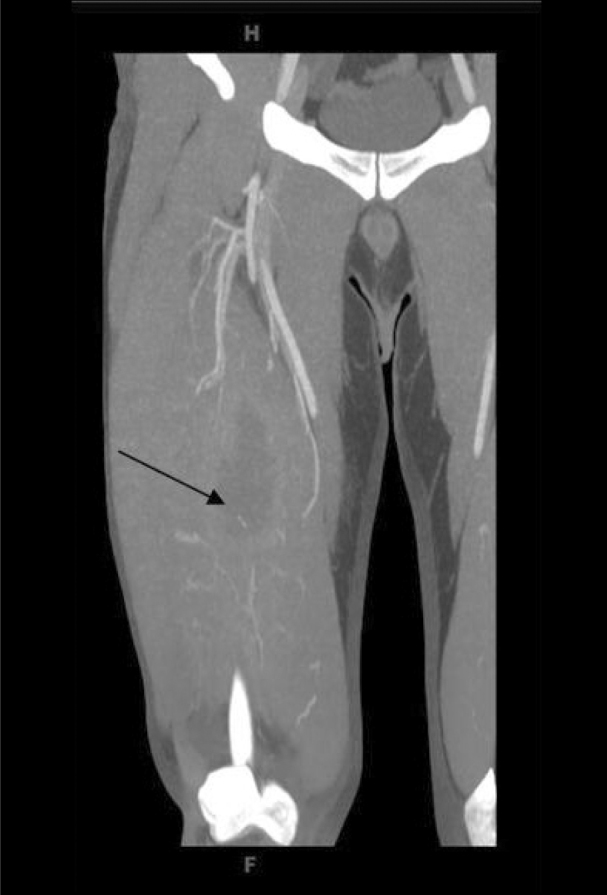

Deep venous thrombosis was suspected however; subsequent two dimensional, pulsed Doppler and color Doppler venous ultrasound of the right lower extremity showed no evidence of thrombus in the right femoral and popliteal veins. CT angiogram was then performed from the right hip through to the plantar arch during intravenous administration of contrast. No evidence of arterial stenosis was shown. Axial, coronal and sagittal images were obtained, and CT revealed a large 9.7 × 3.8 × 3.6 cm fluid collection in the deep anteromedial mid thigh within the quadriceps muscle with peripheral enhancement, likely representing abscess (Fig. 1). An elongated 1.3 cm hyperdensity was seen dependently within the abscess cavity, 5.6 cm deep to the skin surface, suspicious for foreign body. Soft tissue swelling was noted at this level, in addition to a small lateral effusion in the joint space of the right knee. Incision and drainage was performed and the patient was discharged home on oral antibiotics.

Figure 1.

Coronal CT image of the right thigh demonstrating a large 9.7 × 3.8 × 3.6 cm fluid collection in the deep, anteromedial, mid-thigh within the quadriceps muscle with peripheral enhancement.